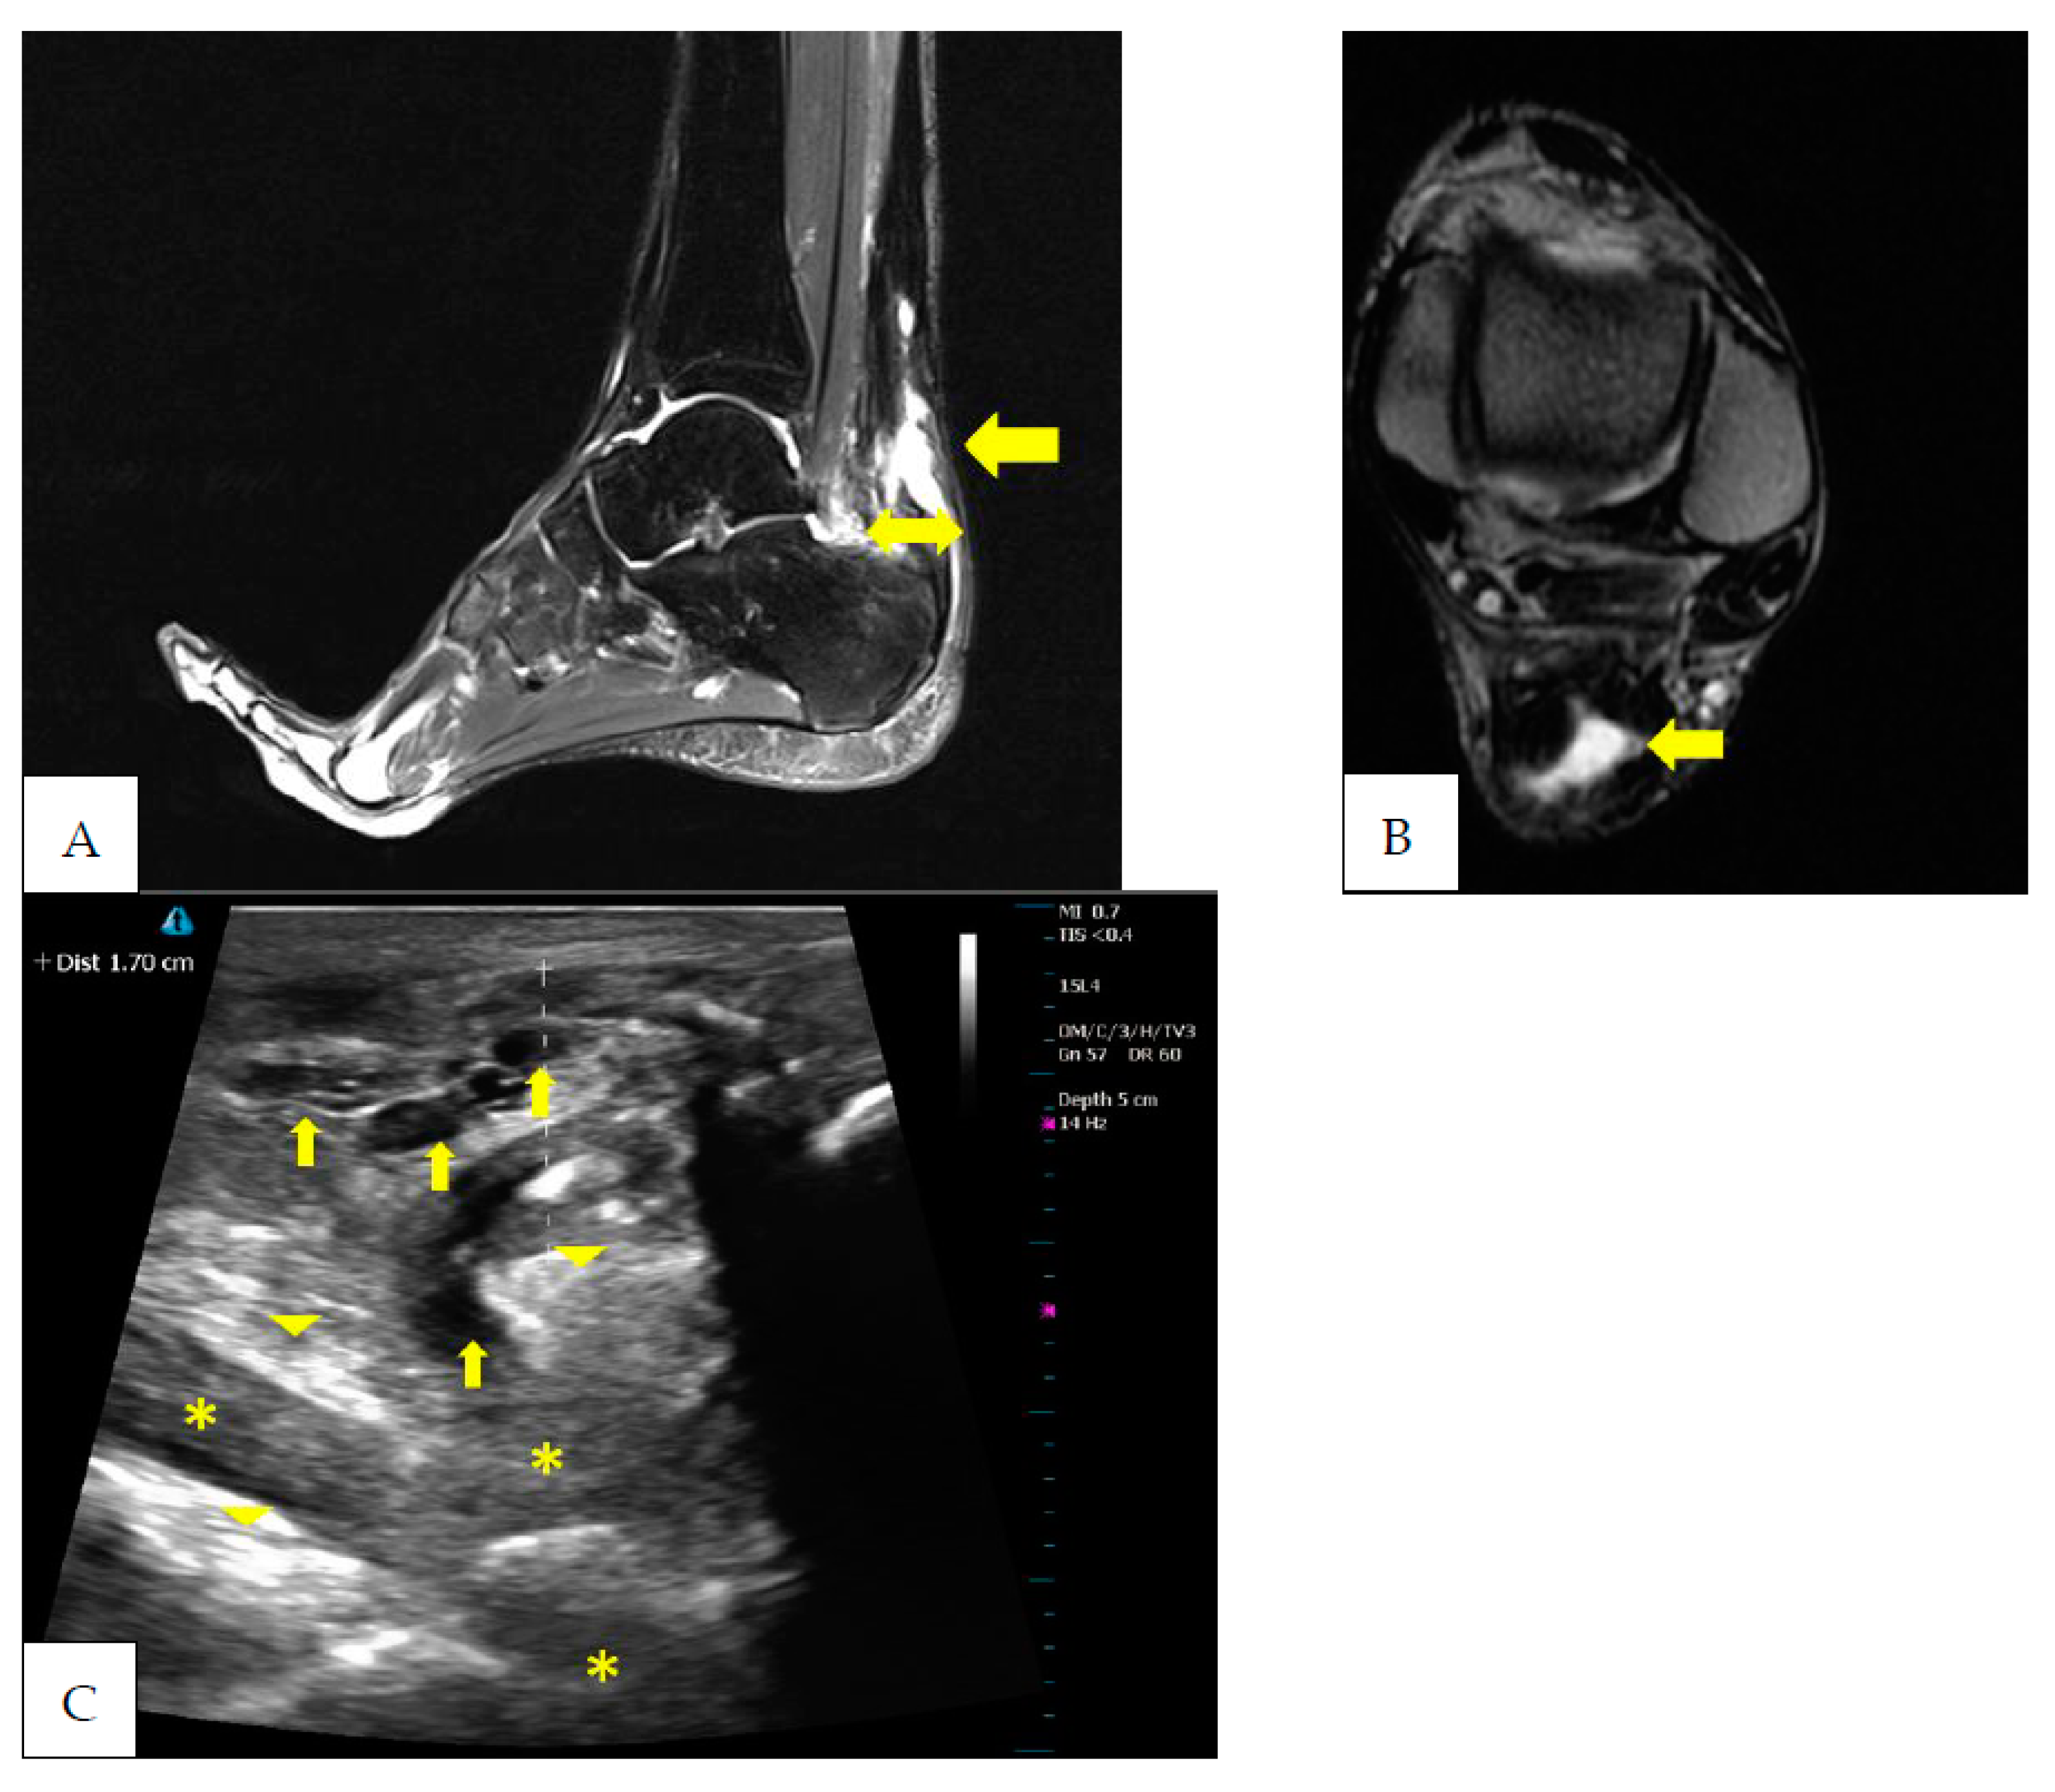

2. Case Presentation